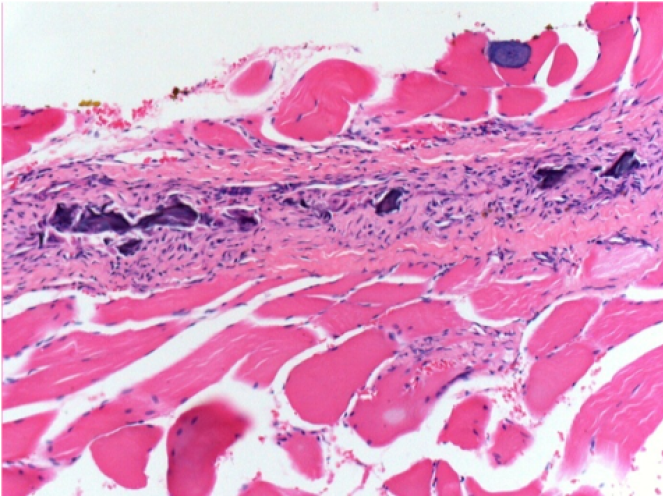

Iniezione Endopeel nel tessuto subcutaneo SC

Scatola 6

0.5 ml ( 5x 0.1ml): Iniezione SC di Endopeel nel tessuto pretibiale subcutaneo SC destro (Dx).

Sx:200x-Controllo-SC

Dx-Giorno10-SC-200X

Dx-Giorno30-SC-200X

Dx-Giorno90-SC-200X

Dx-Giorno210-SC-200X

Dx-Giorno210-SC-400X

Endopeel induce una miofibrolisi selettiva reversibile e una risposta infiammatoria approssimativamente nel periodo di 1 mese.

I cambiamenti dei tessuti muscolari sono quasi completamente reversibili.

Il muscolo é il posto migliore per iniettare Endopeel ,per la sua maggiore efficacità, il controllo e la durata della sua azione.

Nessuna necrosi ne ascesso sono stati osservati durante la sperimentazione.